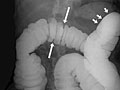

• In a double-contrast or air-contrast study, the colon is first filled with barium, and then the barium is drained out. This leaves only a thin layer of barium on the wall of the colon. The colon is then filled with air. This provides a detailed view of the inner surface of the colon. It makes it easier to see narrowed areas (strictures), diverticula, and swelling.

• A section of colon that did not fill with barium.

• A narrowing (stricture) in the bowel.

• Polyps or growths on the inner wall of the colon.

• Sacs in the colon wall (diverticulosis).

• Problems with defects and swelling (colitis) of the lining of the colon.

• A narrowed segment or a twisted loop of bowel, causing an obstruction.